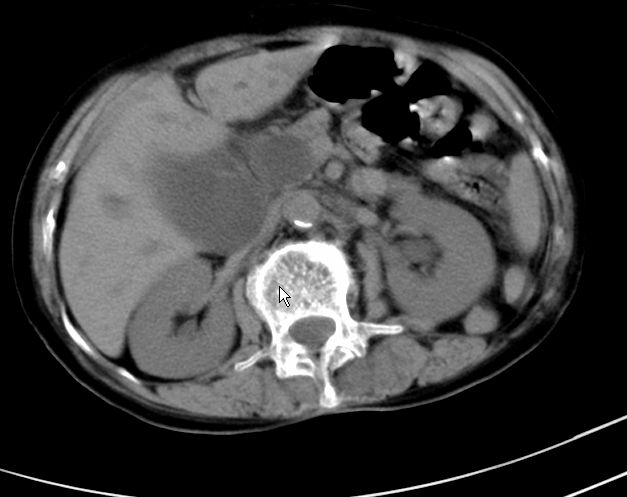

以下是引用zjzjr在2008-12-16 12:49:00的发言:[br]肝内外胆管全程扩张,胆囊明显增大,未见占位征像.建议mrcp.

以下是引用jiangjing在2008-12-16 13:19:00的发言:[br]肝内外胆管全程扩张,胆囊明显增大,扩张胆总管下段径较中上段小,未见胰管扩张,提示胆总管远端梗阻伴感染.建议增强及mrcp 检查

以下是引用朱亮在2008-12-16 12:54:00的发言:[br]胆总管远端应薄层扫描 胆总管逐渐变细 考虑胆系慢性炎症